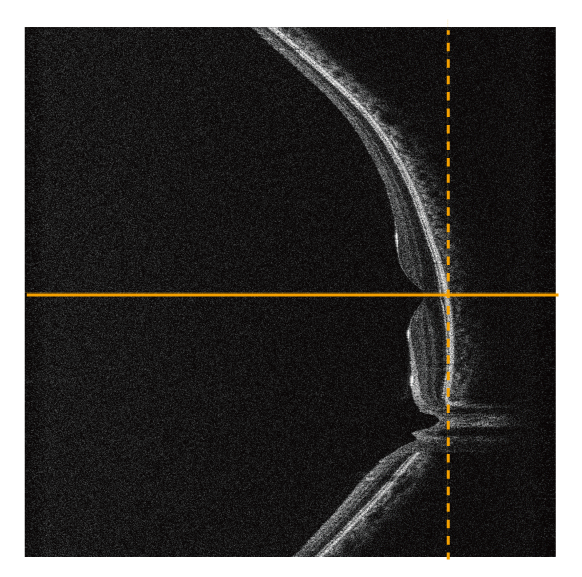

前眼部3Dオートアライメント機構

角膜輝点を検知するオートトラッキング機能を採用し、安定した撮影位置の追従を実現しました。

ジョイスティックを使わずマウスで簡単にアライメント操作が可能です。